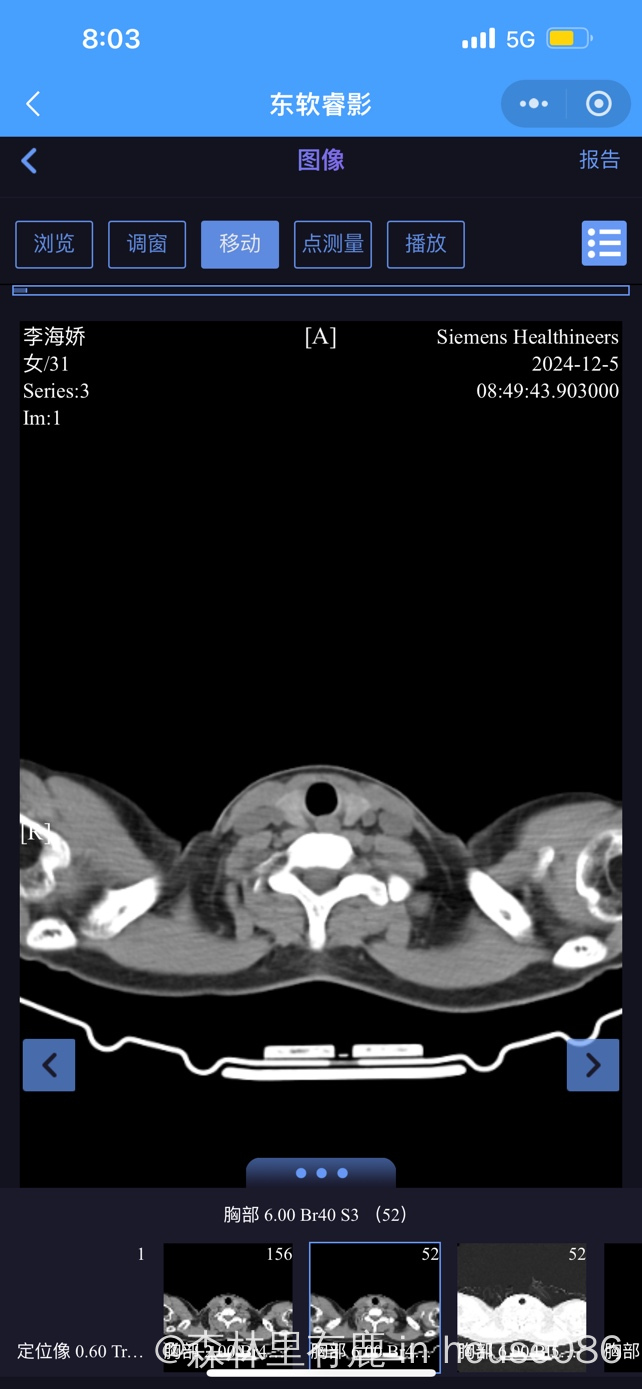

大家帮我看下胸部ct ,医生说右下肺叶很亚严重

现在也不知道是什么性质的肺炎,挂了几天抗生素,还每天会发烧几小时后才退烧

气管镜检查是不是新冠